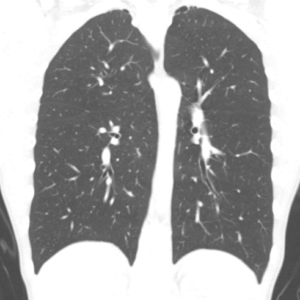

Figure 3: CT scan of thorax in sagittal plane showing bilateral bleb disease in a 14 year old girl who has only been symptomatic on the left. No evidence of residual pneumothorax.